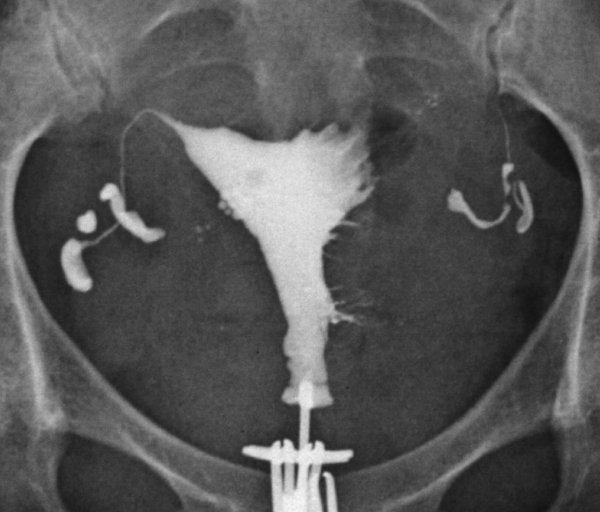

子宮卵管造影で見る通過性回復の様子

FT治療後

②卵管の通過性が回復した画像